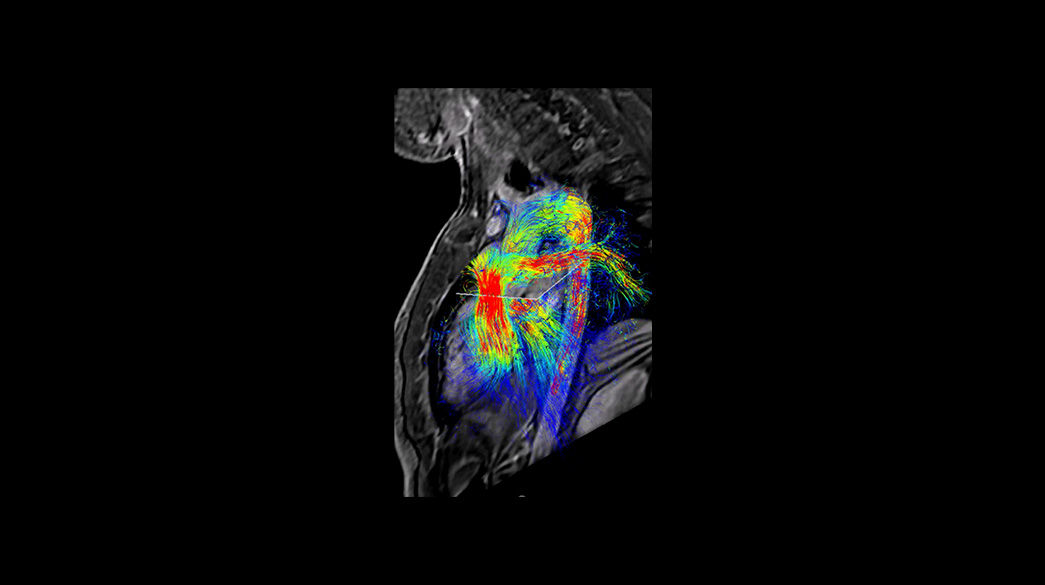

Inhance-Suite1040-x-585

ViosWorks1040-x-585